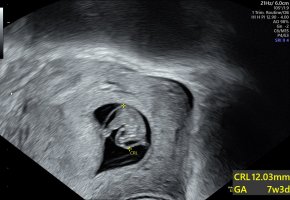

Jeg var på Ultralyd I dag. Ble flyttet fra 6+4 til 7+0.

Så en liten en med hjerteslag.

Vis vedlegget 395064

Til å ligne en bitteliten baby med armer og ben, og litt bevegelse når en kommer over 8 uker (8+3);